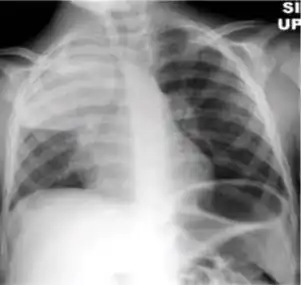

Chest x-ray showing dense opacity pleural effusion in the lower left lung of primary pulmonary TB.